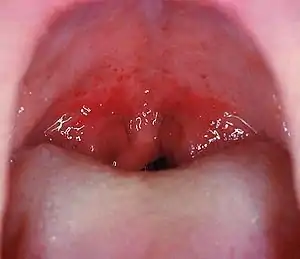

Angines

Ce sont de loin les plus fréquentes conséquences des streptocoques hémolytiques. Environ 45 % des angines rouges et pultacées sont dues à ces streptocoques (l'étiologie des autres angines est virale dans 45 % des cas, celle des 10 % restants est due à des germes divers: diphtérie, staphylocoques, haemophilus, association fuso-spirillaire de Vincent, monilias et mycoplasmas).